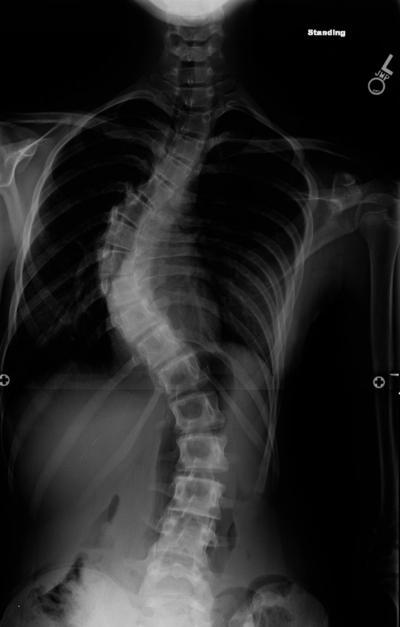

Severe scoliosis linked to rare mutations

Children with rare mutations in two genes are about four times more likely to develop severe scoliosis than their peers with normal versions of the genes, scientists have found. The research at Washington University School of Medicine in St. Louis has identified genetic risk factors that predispose children to develop s-shaped curves in their spines that are dramatic enough to require surgery.

One to 3 percent of the general population has some mild curvature of the spine. In about one in 10,000 children, scoliosis will produce curvature so pronounced that it requires corrective surgery.

(Photo Credit: Matthew Dobbs)